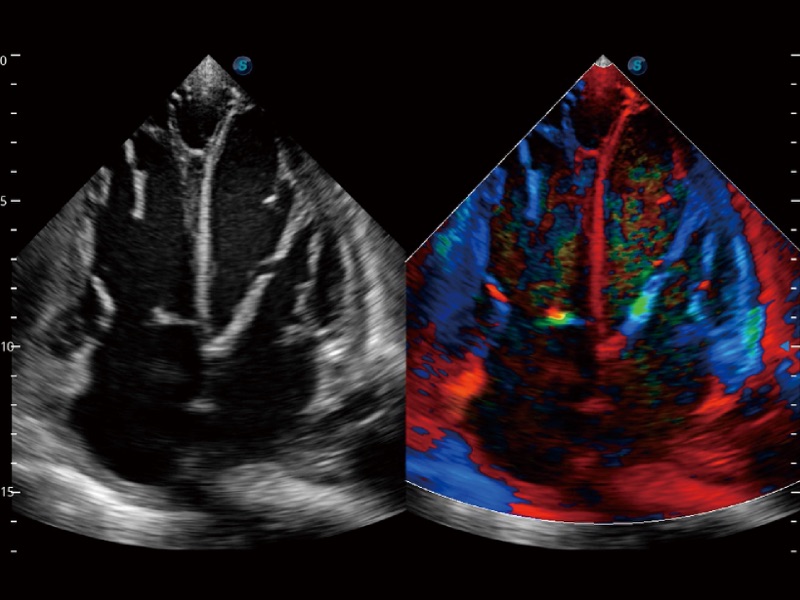

高分辨率血流成像技术提高了对低速血流信号的检测能力。在提高空间分辨率的同时,也克服了血流外溢现象,为用户提供更加真实的血流动力学信息。

心血管应用